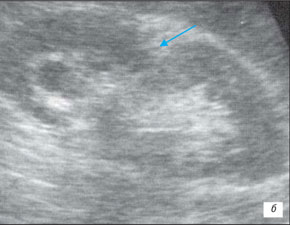

Ехограма розширення порожнинної системи нирки

А – розширення сечоводу:

Б – на тлі сечового міхура.

1 – сечовий міхур, 2 – сечовід

На даній ехограмі спостерігається: зменшення розмірів нирки на стороні поразки; циклічна зміна діаметру сечоводу у верхньому і нижньому відділах; вертикальну спрямованість сечовідно-міхурного викиду, який в нормі має напрям під кутом 30–40° по відношенню до умовної лінії, що сполучає гирла сечоводів.